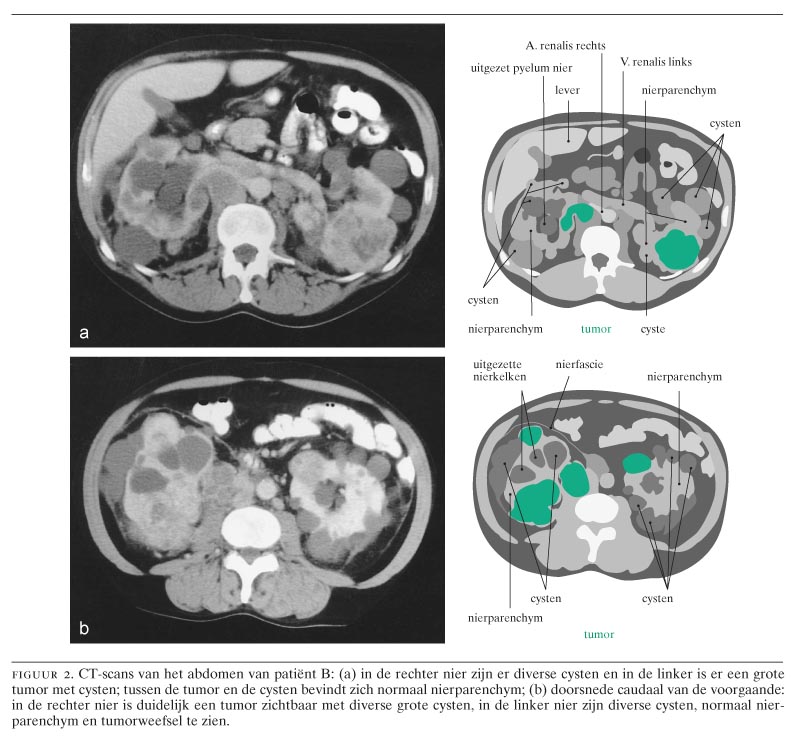

Figuur 2